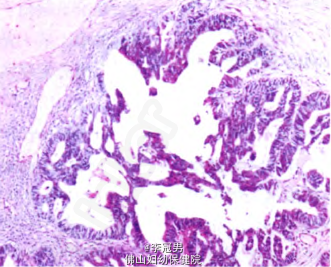

术前诊断:右侧卵巢肿瘤。 处理:在全身麻醉下行开腹探查手术。术中见盆腔无腹水,子宫、双侧卵巢及左侧输卵管均正常,右侧输卵管自壶腹部增粗形成一大小为9.0 cm×8.5 cm×5.0 cm囊肿,表面光滑,包膜完整。术中未行快速冰冻病理检查,行右侧输卵管囊肿剔除术。术后给予对症支持治疗。术后病理检查示:右侧输卵管交界性乳头状囊腺瘤,部分区域癌变,局灶呈肉瘤样分化。2日后,在全身麻醉下行腹腔镜下右侧附件切除术+盆腔淋巴结切除术+大网膜切除术+阑尾切除术+左侧卵巢活检术。术后病理检查示:输卵管交界性乳头状肿瘤(见图1),由浆液性及子宫内膜样上皮成分构成,局部癌变(直径0.2 cm)(见图2),部分分化较差,呈肉瘤样癌结构(见图3)。免疫组化:AEI/AE3(分化较好区+++,分化差区+),CK7(分化好区+,分化差区一),CK20(分化较好区+,分化较差区一),R(一),Vimentin(+),Ki-67指数15%一30%。卵巢、阑尾、大网膜及盆腔淋巴结均未见肿瘤(0/30)。术后诊断为:右侧输卵管恶性苗勒管混合瘤。术后给予卡铂+紫杉醇3疗程化疗。

患者术后6个月定期随访无特殊不适。 讨论:恶性苗勒管混合瘤(MMMT)是女性生殖道恶性肿瘤之一,是罕见的高度恶性肿瘤。该肿瘤最常见于子宫内膜,其次是阴道、官颈、卵巢,输卵管最少见,仅占所有MMMT的4%。多数患者为50—60岁的绝经后女性,平均年龄57.5岁。其典型组织学特点为癌和肉瘤样成分混合存在,癌样成分常为子宫内膜样、透明细胞样或乳头状浆液性,分化较差;肉瘤样成分似平滑肌肉瘤或纤维肉瘤,半数以上可出现骨骼肌、骨、软骨或脂肪等异源性成分输卵管癌变往往没有典型的临床症状,以往以盆腔包块、阵发性阴道排液和腹痛“三联征”作为输卵管癌的术前诊断依据。但近年来发现临床上同时出现“三联征”的病例并不多,而以盆腔包块伴阴道排液或阴道不规则流血的“二联征”多 见。本例患者术前也没有明确的“三联征”表现,而是以停经及盆腔包块为主要的临床表现,实属少见,最终患者因“附件肿瘤”进行手术,术中发现病变源于输卵管,术后病理检查提示输卵管交界性乳头状肿瘤,由浆液性及子宫内膜样上皮成分构成,局部癌变,部分分化较差,呈肉瘸样癌结构,符合MMMT的病理学诊断。